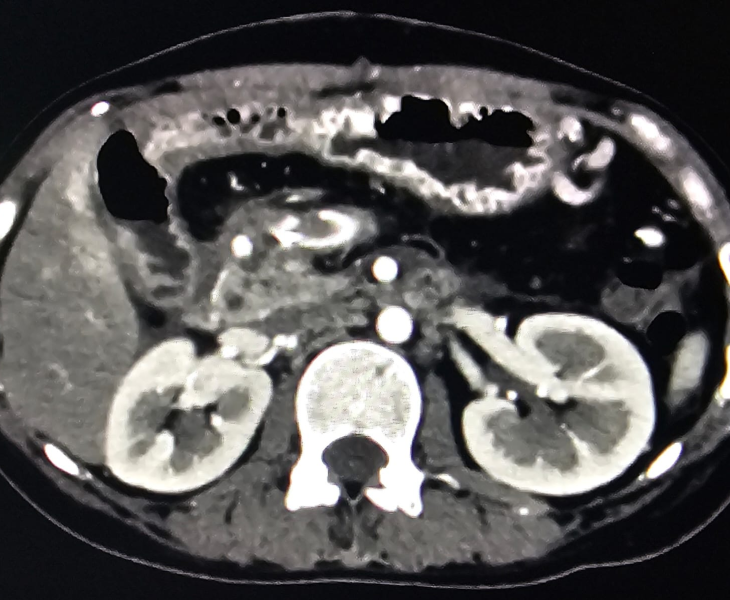

We use CT angiography and catheter angiography to identify the bleeding vessel precisely and then perform targeted embolization to seal it while preserving as much normal organ blood supply as possible.

- Post‑embolization check: repeat angiography confirms complete sealing with preserved flow to normal tissues.

- Follow‑up imaging in selected cases to confirm durable occlusion